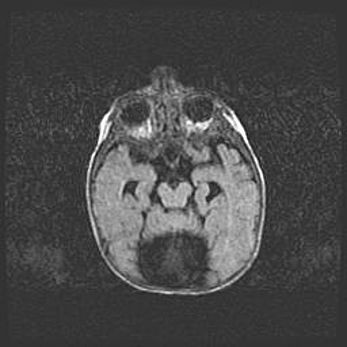

Аномалия Денди-Уокера. Признаки гипоплазии мозолистого тела.

Возраст: 5 месяцев 3 дня

Вес: 5550 г

Пол: мужской

Окружность головы: 39 см

Срок гестации: 40 недель

Аномалия Денди-Уокера – это порок развития головного мозга, для которого характерна триада симптомов: гипотрофия или аплазия червя мозжечка и/или полушарий мозжечка, расширение четвёртого желудочка с формированием ликворной кисты задней черепной ямки, гипертензионная гидроцефалия различной степени.

Гипоплазия мозолистого тела относится к дефектам внутриутробного этапа развития мозговой ткани, возникающим в процессе закладки структур головного мозга, что происходит на начальных этапах развития эмбриона.